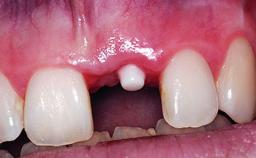

A 32-year-old female Caucasian patient with a compromised maxillary right central incisor was referred to us by a general dentist. Her chief complaints were discomfort and mobility of tooth 11 with unsatisfactory esthetics due to discoloration. The patient reported a previous trauma, some years earlier, as the origin of pathology on the afflicted tooth. Anamnesis was negative for any other dental or periodontal pathology in the remaining dentition. The patient did not take any medication and reported to be a light smoker (5–10 cigs/day). She had high esthetic expectations of her treatment. The extraoral examination revealed a high smile line with full exposure of her maxillary teeth and surrounding soft tissue in the area between the second premolars.

Soft Tissue Grafting Staged

Placement Protocol Early or late implant placement

Loading Protocol Conventional or early